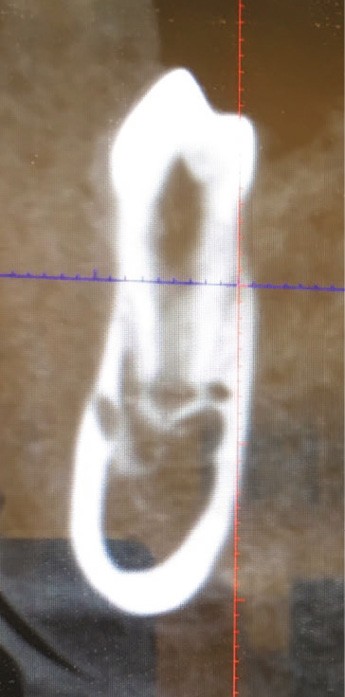

Un bilan radiologique 3D (Cone Beam CT) est prescrit dans le but d’évaluer, avec l’équipe de chirurgie du Dr Jean-Luc Charrier (Hôpital Bretonneau), la possibilité de transplantation d’une prémolaire du secteur 4 vers le secteur 1 et de définir le meilleur transplant possible entre 44 et 45. Sont analysées les dimensions du site receveur ainsi que l’anatomie, la position et l’état de maturation radiculaire des prémolaires candidates à la transplantation (fig. 3).

- Concernant 45 :

- sa situation endo-osseuse (à l’abri de la flore bactérienne buccale et avec un desmodonte immature car non soumis aux stimuli occlusaux, facilitant une avulsion atraumatique) et son immaturité radiculaire franche (apex largement ouvert favorisant la revascularisation) font d’elle un transplant de choix ;

- mais il existe une proximité nette entre la couronne de 45 et la racine de 44, (augmentant le risque de lésion de 44 lors de l’avulsion de 45), et un rapport étroit entre la couronne de 45 et la corticale osseuse vestibulaire (augmentant le risque de lésion parodontale post-extractionnelle) ;

- enfin, 45 présente une longueur radiculaire encore courte risquant d’amener à un rapport couronne/racine limite in fine si l’édification radiculaire devait être stoppée après la transplantation de cette dent ;